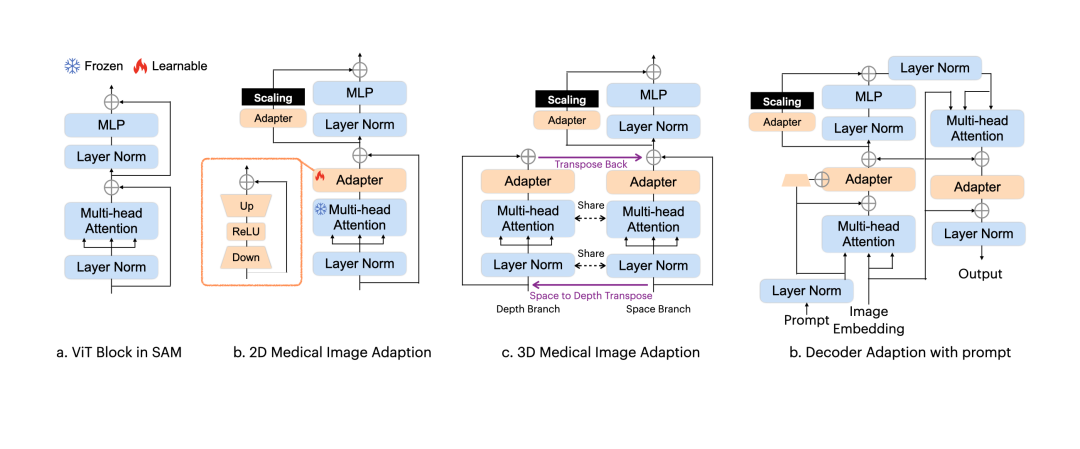

3DSAM-adapter:为了适应3D空间信息,提出了一种修改图像编码器的方案,使原始的2D变换器能够适应体积输入。

Medical SAM Adapter

Medical SAM Adapter:专为SAM设计了一个通用的医学图像分割适配器,能够适应医学数据的高维度(3D)以及独特的视觉提示,如 point 和 box。